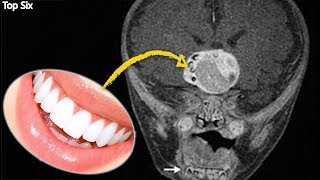

¿PODRÁS TERMINAR DE VER ESTE VIDEO? EXTRAÑOS CASOS MÉDICOS QUE TE ASOMBRARAN ─ TOPSIX